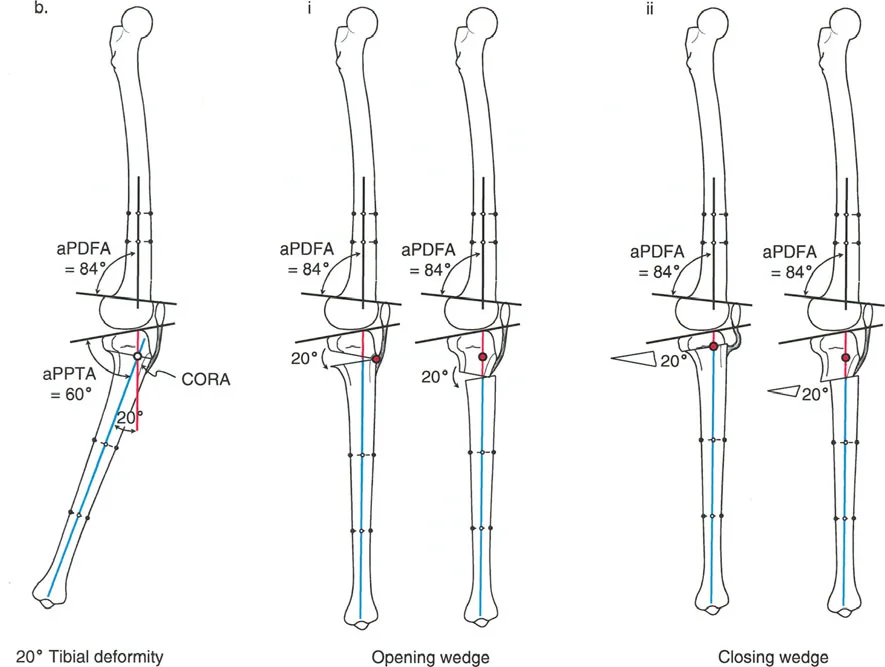

تتضمن جراحة قطع العظم قطع العظم (عادة عظم الفخذ أو الساق) وإعادة تشكيله لتغيير محاذاة المفصل. يمكن أن يكون القطع:

- قطع العظم بالوتد المفتوح (Opening Wedge Osteotomy): يتم عمل قطع في العظم ثم فتح فجوة صغيرة تُملأ غالبًا بطعم عظمي، مما يطيل الجزء المعني من العظم ويصحح المحاذاة.

- قطع العظم بالوتد المغلق (Closing Wedge Osteotomy): يتم إزالة جزء صغير من العظم على شكل وتد، ثم تُغلق الفجوة وتُثبت العظام، مما يقصر الجزء المعني ويصحح المحاذاة.

غالبًا ما ترتبط خشونة الركبة الإنسية بالانحراف الأفحج (Genu Varum). يهدف العلاج إلى تحويل الحمل من الحجرة الإنسية المتضررة إلى الحجرة الوحشية السليمة.

- قطع العظم الظنبوبي العلوي (High Tibial Osteotomy - HTO):

- يُعد هذا الإجراء الأكثر شيوعًا لعلاج خشونة الركبة الإنسية مع الانحراف الأفحج.

- يتم عمل قطع في الجزء العلوي من عظم الساق (الظنبوب)، ثم يتم تصحيح الانحراف الأفحج عن طريق فتح وتد (Opening Wedge) على الجانب الإنسي أو إزالة وتد (Closing Wedge) على الجانب الوحشي.

- قطع العظم الفخذي البعيد (Distal Femoral Osteotomy - DFO):

- قد يكون ضروريًا إذا كان التشوه الأفحج يتركز في عظم الفخذ.

ترتبط خشونة الركبة الوحشية غالبًا بالانحراف الأروح (Genu Valgum). يهدف العلاج إلى تحويل الحمل من الحجرة الوحشية المتضررة إلى الحجرة الإنسية السليمة.

- قطع العظم الفخذي البعيد (Distal Femoral Osteotomy - DFO):

- يُعد الخيار الأكثر شيوعًا، حيث يتم عمل قطع في الجزء السفلي من عظم الفخذ لتصحيح الانحراف الأروح.

- قطع العظم الظنبوبي العلوي (High Tibial Osteotomy - HTO):

- يمكن استخدامه إذا كان التشوه الأروح يتركز في عظم الساق.

- ملاحظة هامة: يجب تصحيح LCOA إلى محاذاة محايدة (MAD = 0 مم) فقط، على عكس MCOA التي غالبًا ما يتم تصحيحها بشكل مفرط قليلاً إلى وضعية الأروح. هذا لتجنب تحميل زائد على الحجرة الإنسية.